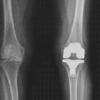

A retrospective analysis was conducted on data from 300 who underwent robotic TKA using a system that incorporates computed tomography (CT)-derived bone models. TEA and PCA were measured preoperatively on CT . Each patient underwent pre-operative CT scans of the ankle, knee, and hip and was instructed to stretch the knee joints as far as feasible. Jplanner software (Java, San Diego, CA) was used to segment all of the scans. A three-dimensional (3D) replica of the patient’s degenerative knee joint was generated by segmenting the femur and tibia bones. The study included patients who required a total knee replacement due to OA in their knees. The study excluded patients with trochlear dysplasia, arthritis with inflammation, and post-traumatic or septic arthritis. To best identify the median sulcus, two lines of reference were drawn across the axial portion of the femur’s distal end, where the femoral epicondyles intersect. The “posterior condylar axis” (line 1) is formed by the posterior areas of both the lateral and medial condyles, whereas (line 2) “the surgical transepicondylar axis” connects the most prominent region of the “lateral epicondyle” to the “medial epicondyle’s median sulcus” (Fig. 1). “The PCA is the angle formed by the surgical TEA and the posterior condylar line” (Fig. 2a and b, Fig. 3) depicts “the surgical TEA (surg TEA) [9], the anatomic TEA (anat TEA) [10], and the angle between them.”